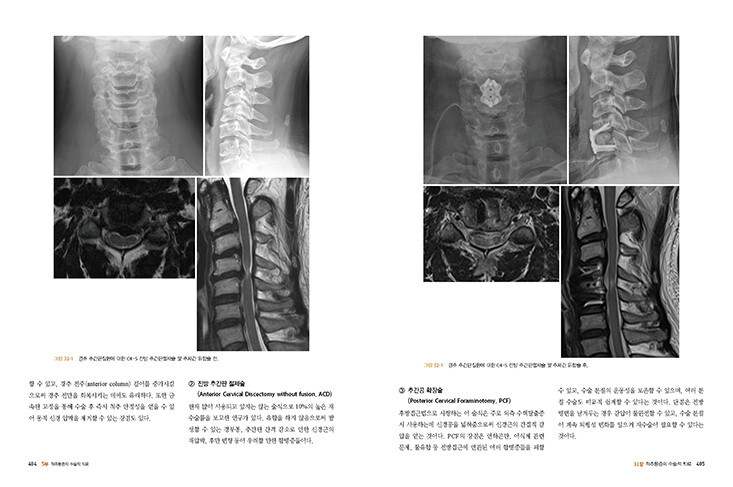

31장 척추통증의 최소침습 수술적 치료

32장 척추통증의 수술적 치료